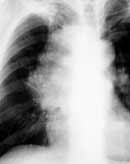

Предполагается, что химиотерапия является фактором отбора наиболее устойчивых к цитостатикам более дифференцированных клеток, которые получают возможность быстро размножаться и формировать новые очаги опухоли. Видимо этот факт объясняет высокую частоту (по разным данным от 33 до 50%) местных рецидивов при консервативном лечении МКРЛ (Рис. 3).

Рис. 3. Рак правого верхнедолевого бронха. (а) Обзорная рентгенограмма в прямой проекции до лечения.

Рис. 3. Рак правого верхнедолевого бронха. (б) Обзорная рентгенограмма в прямой проекции после 2 курхов химиотерапии (резорбция опухоли и метастазов в лимфоузлы средостения).

Рис. 3. Рак правого верхнедолевого бронха. (в) Обзорная рентгенограмма в прямой проекции до лечения. Рецидив опухоли через 10 месяцев.